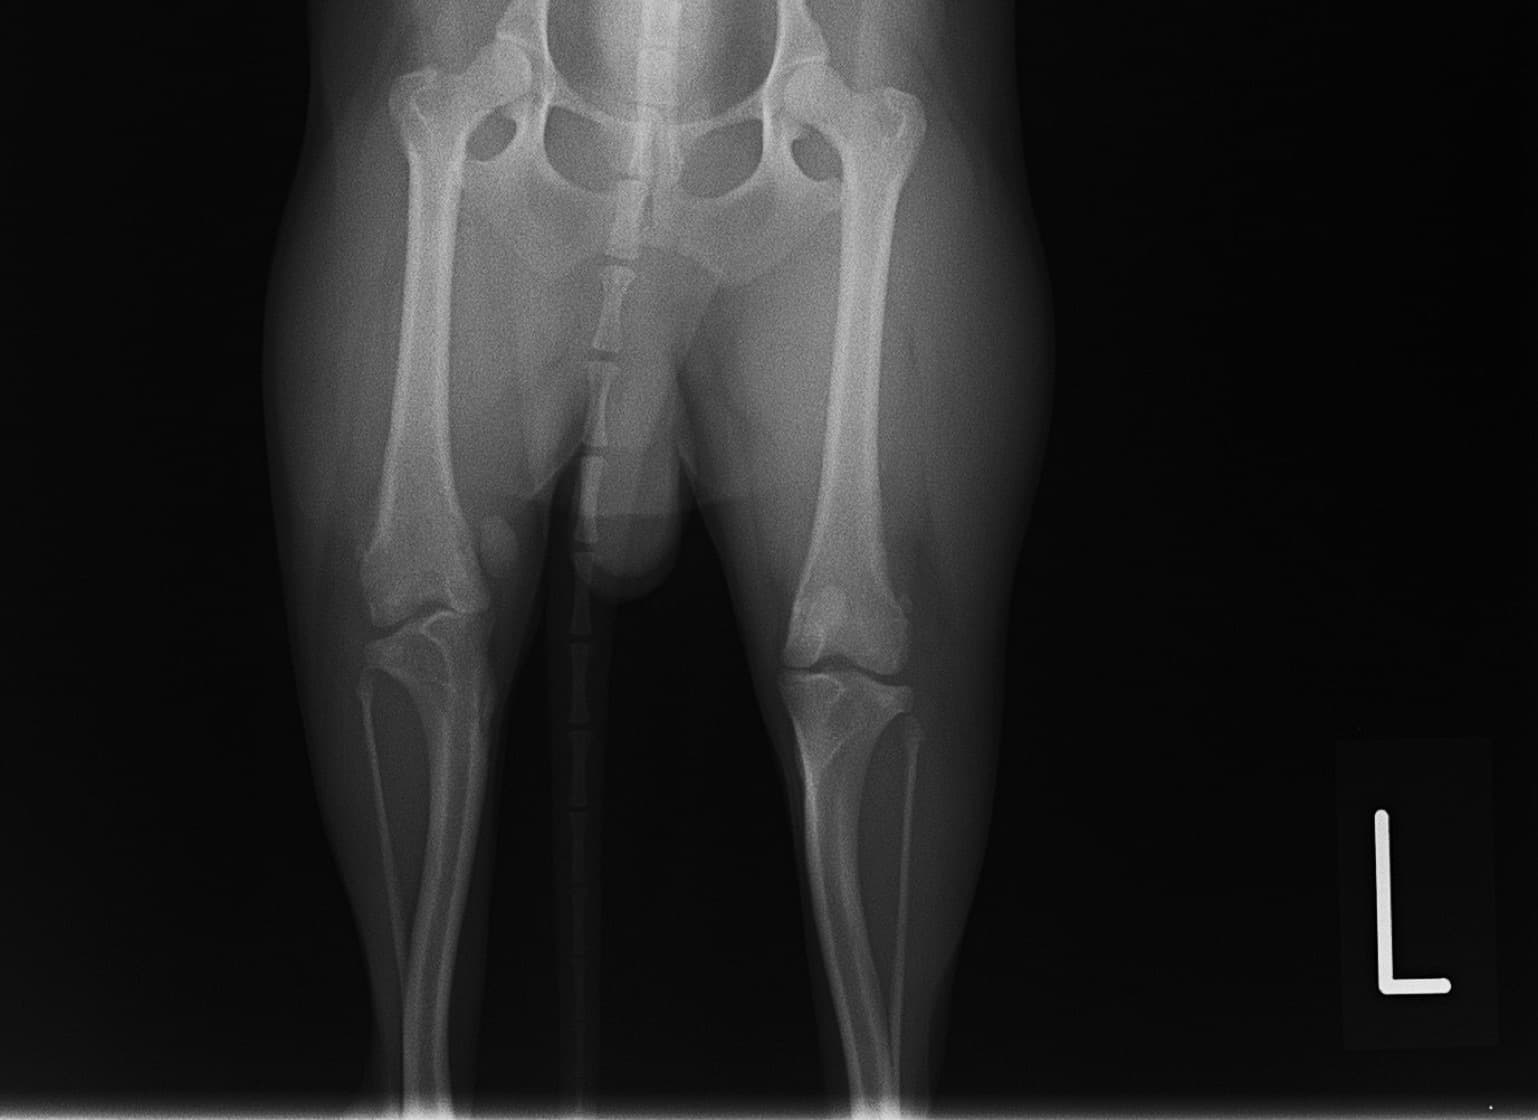

内方膝蓋骨脱臼の発生原因は内反股と大腿骨頸の前捻であると結論づけている研究があります。また、遺伝的要素が重要と考えられており、大腿四頭筋機構の異常、股関節異常、後肢の変形との関連などが報告されておりますが、現在でも正確な病因あるいは発生機序は分っておらず、治療方針や合併症の問題に関して議論が続いています。10kg以下の小型犬に多く認められる傾向があること、大型犬でも内方への脱臼が全体の75~90%を占める傾向があります。